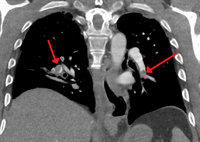

On CT scan, pulmonary emboli can be classified according to the level along the arterial tree.

Segmental and subsegmental pulmonary emboli on both sides